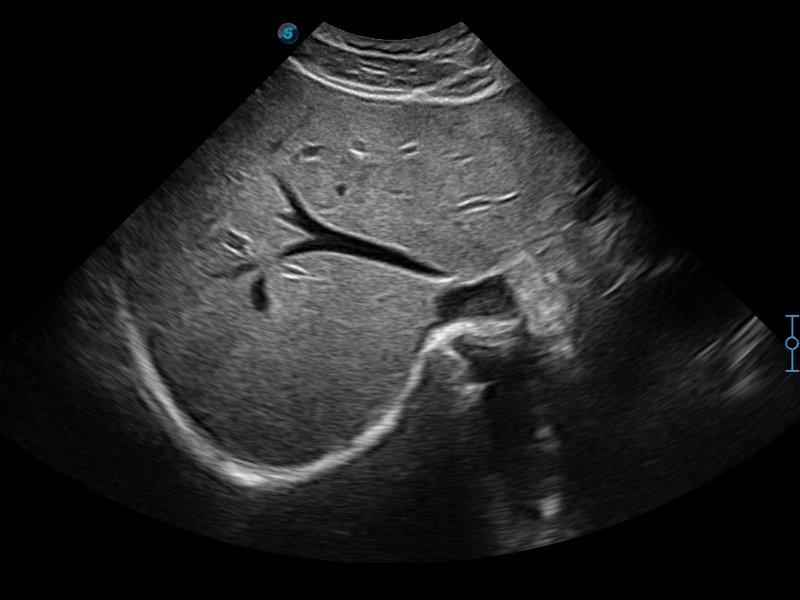

開立醫(yī)療通過不斷的技術(shù)創(chuàng)新,為大眾的生命健康提供持續(xù)關(guān)愛。P12 Plus采用全新一代超聲成像平臺,新平臺旨在將真實(shí)還原組織解剖結(jié)構(gòu)作為首要目標(biāo)。平臺采用全新集成化硬件模塊,搭載新一代芯片,系統(tǒng)性能得到大幅提升,為您的診斷提供了豐富的臨床信息。優(yōu)異的圖像表現(xiàn),豐富的探頭配置,全面的應(yīng)用功能,為您日常診斷提供了可靠的助手。

P12 Plus

彩色多普勒超聲診斷系統(tǒng)